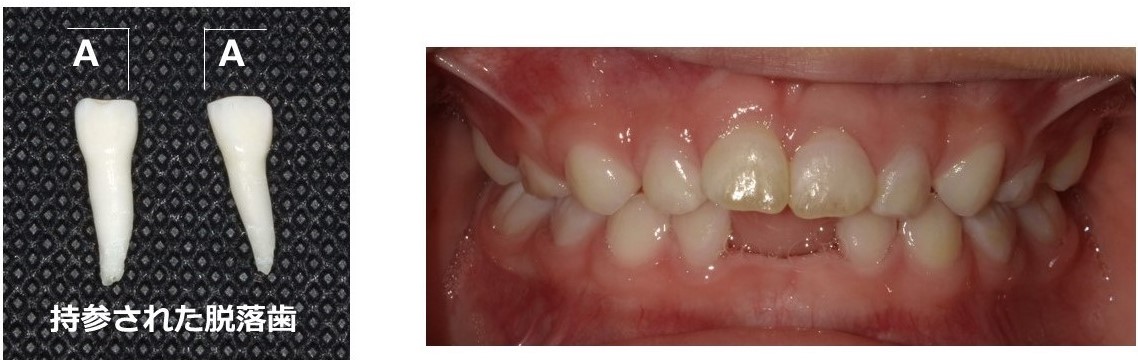

歯学生が使用している小児歯科学の教科書には、低ホスファターゼ症は、アルカリホスファターゼという酵素量の低下により、歯または骨に症状を示す疾患であると記載されています。特に強調されているのが、「発生頻度が10〜15万出生あたり1人」ということと「歯の症状は乳歯の早期脱落」であるという2点です。また、典型例として、歯根が長いまま脱落した乳歯の写真(図1)が掲載されているのをよく見かけます。歯の脱落は、アルカリホスファターゼの量の低下によって、歯根表面のセメント質に形成不全が生じ、歯根と歯槽骨との接着が不十分になるために起こるとされています。

(図1)低ホスファターゼ症の一例(軽症なタイプ:4歳3か月女児)

2歳頃に下顎両側乳切歯が脱落したとのこと。隣在歯にも動揺を認める。